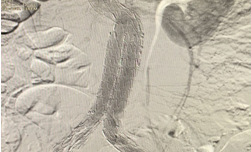

The Abdominal Aortic Aneurysm (AAA) was extending from the infra-renal aorta to both Common iliac arteries. Endovascular Aneurysm Repair (EVAR) was planned. Generally, an EVAR is done by surgically exposing femoral arteries bilaterally to take the grafts inside the aorta for Endovascular repair. We did the EVAR completely percutaneous- avoiding any surgical exposure. No Groin Cut, No surgical femoral artery exposure # SIMPLY Percutaneous. The patient Got discharged in 48 Hrs. It’s actually technically challenging to create 2 X two sets of pre-close sutures / Bilateral femoral for 20F (6mm) holes on Common femoral arteries. The procedure was done with suture closure of Bilateral 6 mm holes over the femoral without exposing the femoral - that’s the beauty.

suture-less-endovascular-aneurysm-repair-for-abdominal-aortic-aneurysm-2